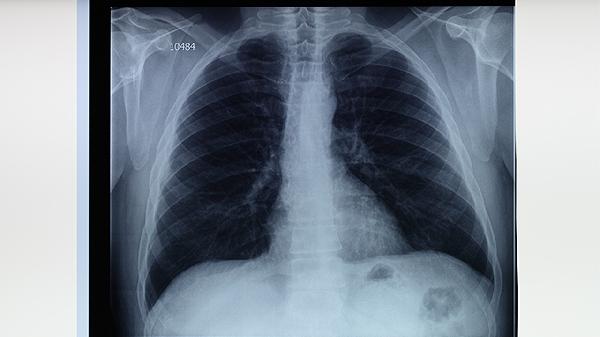

可發(fā)現(xiàn)肺部典型的上葉尖后段浸潤影、空洞形成等病變特征。對(duì)于痰涂片陰性但高度懷疑肺結(jié)核的患者具有重要篩查價(jià)值。需注意部分早期結(jié)核或免疫抑制患者可能無典型影像學(xué)表現(xiàn)。

能更清晰顯示微小病灶、淋巴結(jié)鈣化及支氣管播散灶,對(duì)復(fù)雜病例的診斷優(yōu)于普通X線。高分辨率CT可發(fā)現(xiàn)2毫米以上的粟粒樣結(jié)節(jié),對(duì)血行播散型結(jié)核的診斷敏感性可達(dá)90%。